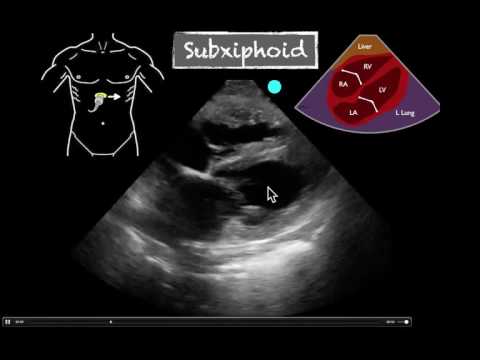

Basic Applications : Cardiac – Subxiphoid Scanning Technique

POCUS Series – Cardiac – Subxiphoid